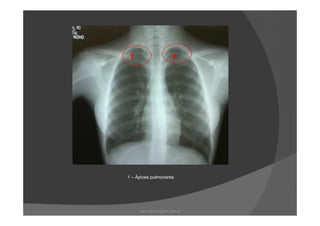

1 – Ápices pulmonares

1 – Ápicespulmonares www.playmagem.com.br